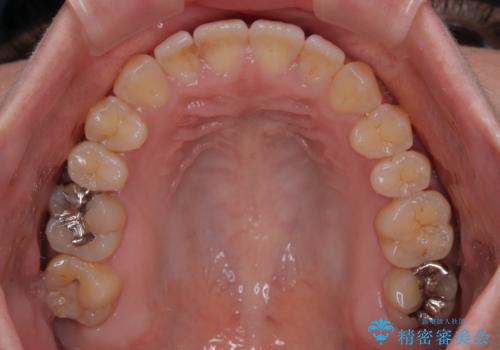

- 極端な開咬を気にして来院された患者様です。

開咬の方の特徴として、幼少期の指しゃぶりの癖や、強い舌の突出癖が挙げられます。

こちらの患者様も強い舌の突出癖が認められたため、矯正治療を行うにあたり、舌のトレーニングをしっかりと行っていただくように指示をいたしました。

開咬はインビザラインが得意とする歯列不正であるため、舌のトレーニングを行いながら、インビザラインにて矯正治療を行うこととしました。

担当医としては、もっと上下の前歯を接触させるところまで治療を進めたいという思いがありますが、今まで咀嚼できなかったものが食べられるようになったということで、この状態で治療終了となりました。